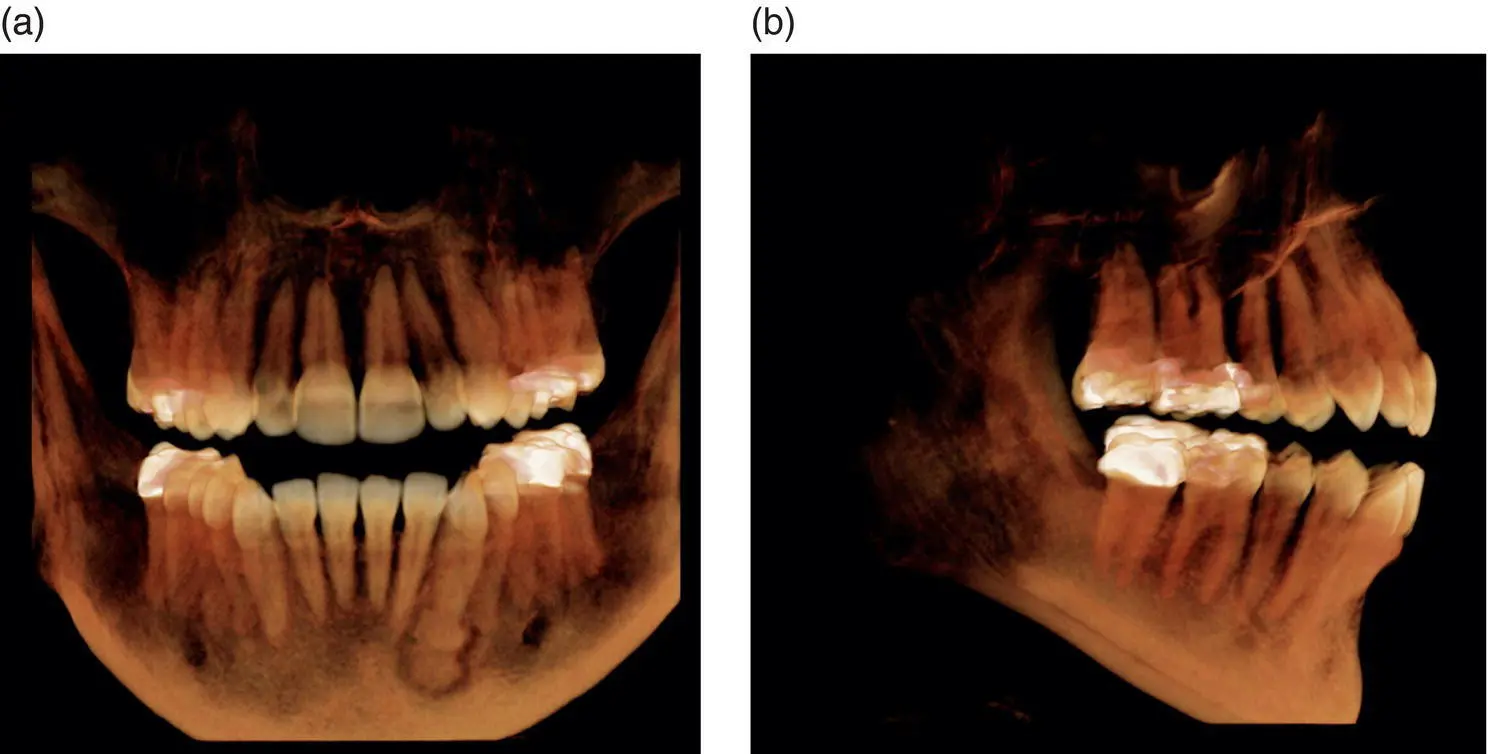

Figure 1.4.Axial (A), coronal (C), sagittal (S), and reconstructed 3D views from medium FOV.